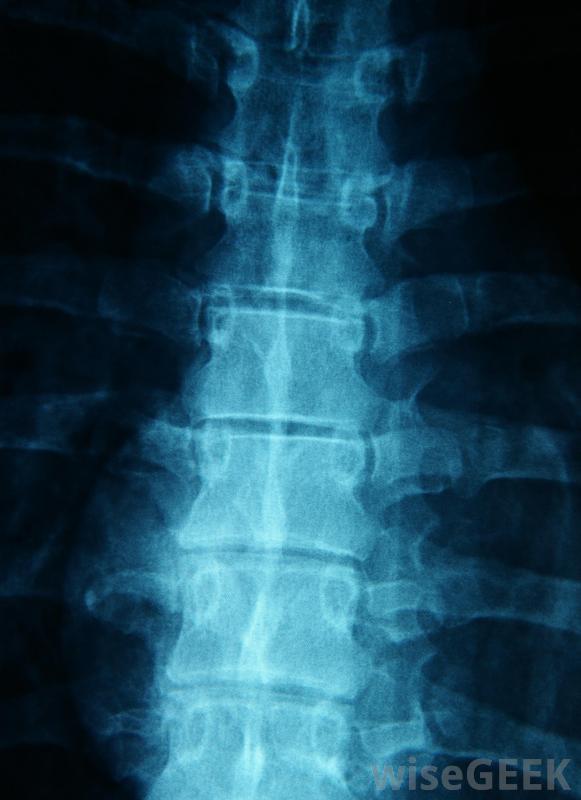

在醫院里,可以佩戴背帶,醫生可以對背部進行x光和計算機斷層掃描,以尋找胸部壓縮性骨折的跡象。醫生還會進行徹底的身體檢查,以確定患者是否感到麻木、刺痛、虛弱,或認知障礙。根據患者的情況和事故中可能發生的任何其他傷害,專家可能需要提供緊急藥物和治療,以穩定呼吸、生命體征和意識。

脊柱的X光片將用于幫助診斷胸部壓縮性骨折。